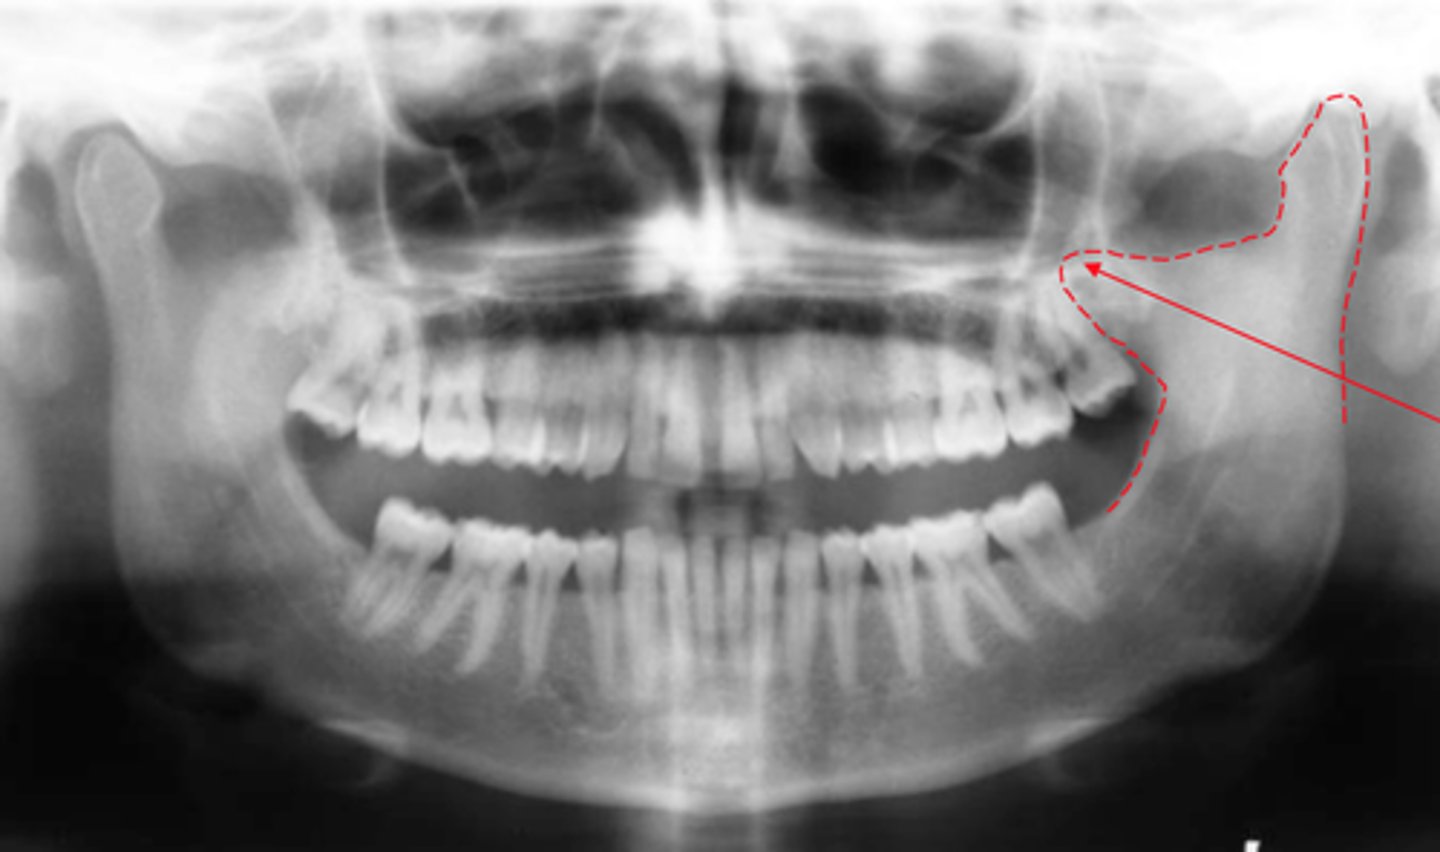

Identify if this is a:

A. Panoramic

B. Cross-sectional image

C. Periapical

D. Bitewing

E. Occlusal

A

describe the general orientation or relationship of an object to an panoramic

Most common extraoral image

Shows entire maxilla and mandible

Single image